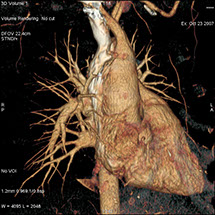

• Les pathologies thoraciques (infection, tumeurs …).

On peut faire ressortir le contraste de certains tissus, en particulier des vaisseaux sanguins, en injectant un produit dit "de contraste" (contenant de l'iode) qui a la propriété de fortement absorber les rayons X et donc de rendre très visibles les tissus où ce produit est présent (qui apparaissent alors hyperdenses, c'est à dire plus "blancs" sur l'image).

Grâce aux scanners multidétecteurs (ou multi-barrettes) à acquisition spiralée, on obtient une exploration très précise d'un large volume du corps humain pour un temps d'acquisition de quelques dizaines de secondes.